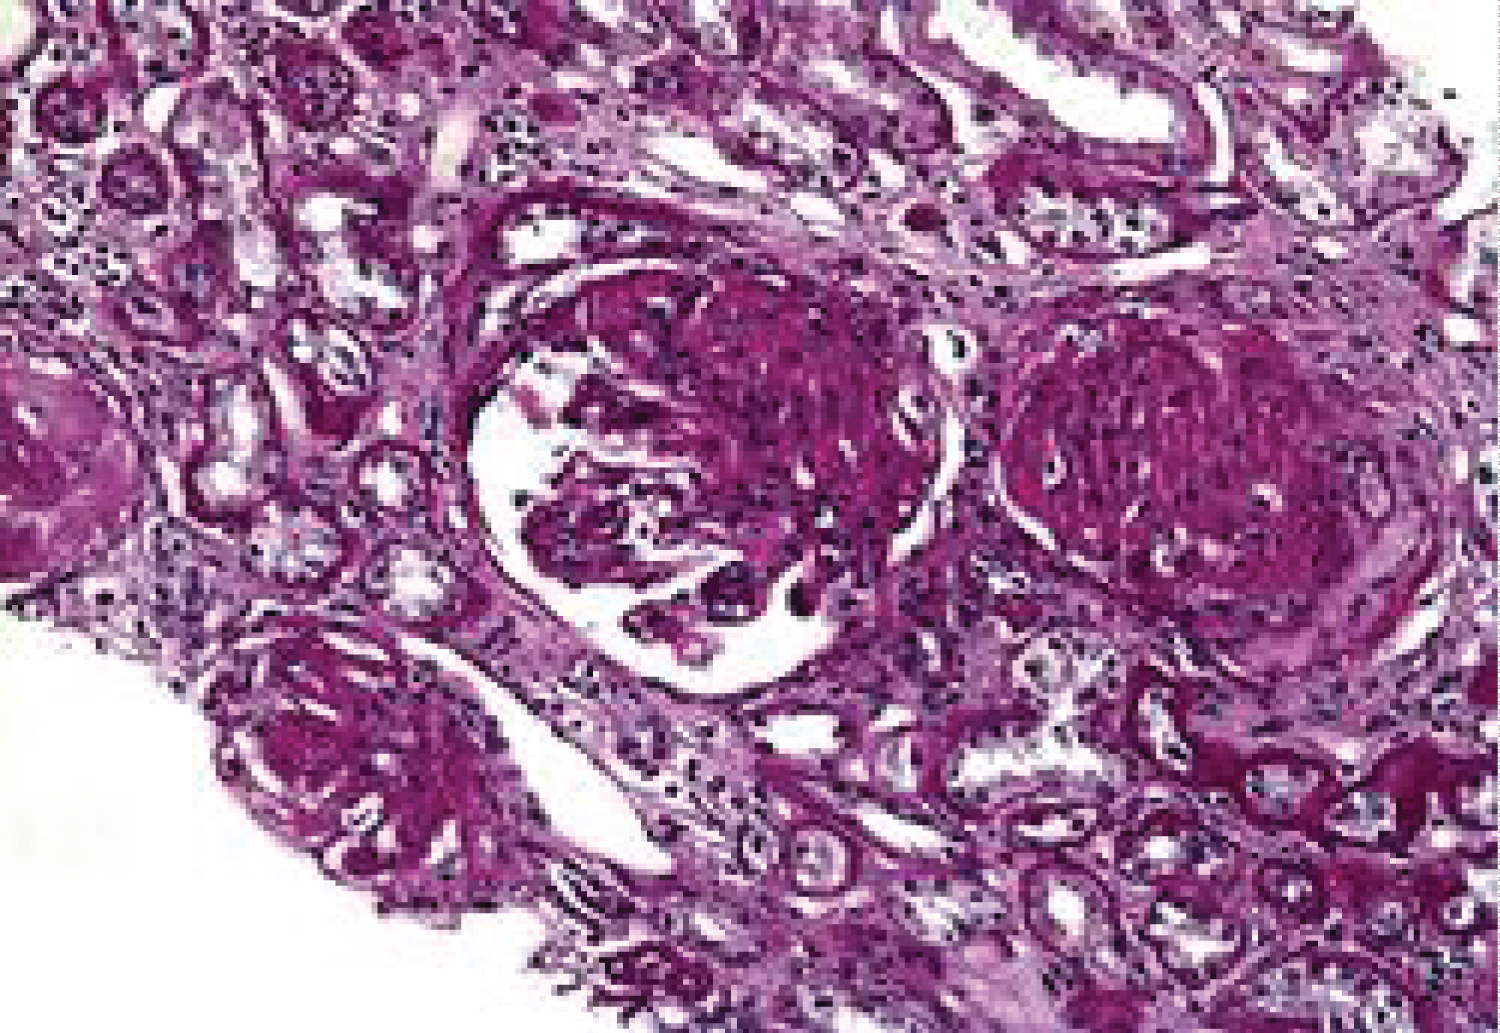

Tissue histology of the kidney biopsy specimen showed

Advanced global glomerulosclerosis, with diffuse glomerulosclerosis (> 90% global sclerosis) representing healing of previously inflamed tissues. Advanced tubulointerstitial disease, with tubular atrophy and interstitial fibrosis. Atrophic tubules contain PAS-positive hyaline casts, some small atrophic tubules without prominent lumen. Marked interstitial inflammatory cellular infiltration.

Stage VI Lupus nephritis with resolving serositis (Figure 1).

Figure 1: Photomicrograph showing lupus nephritis class VI with advanced sclerosing glomerular disease and tubular atrophy (x300). View Figure 1